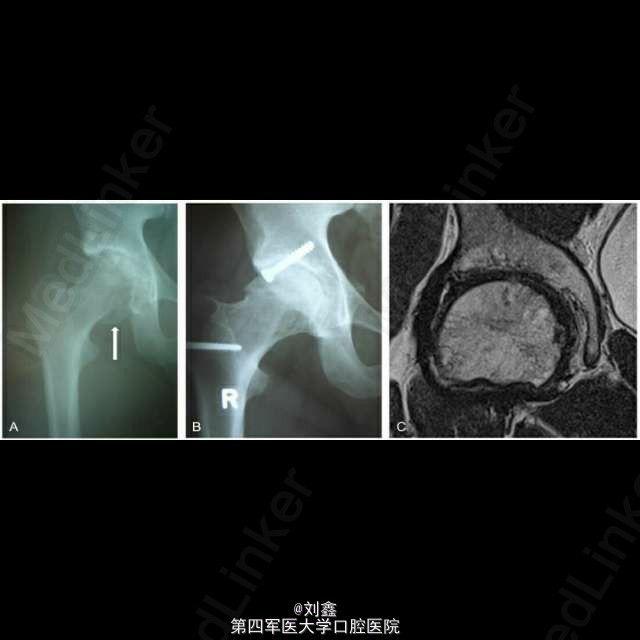

自体软骨移植治疗股骨头骨折

患者男,34,股骨头骨折,采用自体软骨移植。磁共振扫描确认股骨头骨折块与移植软骨愈合。